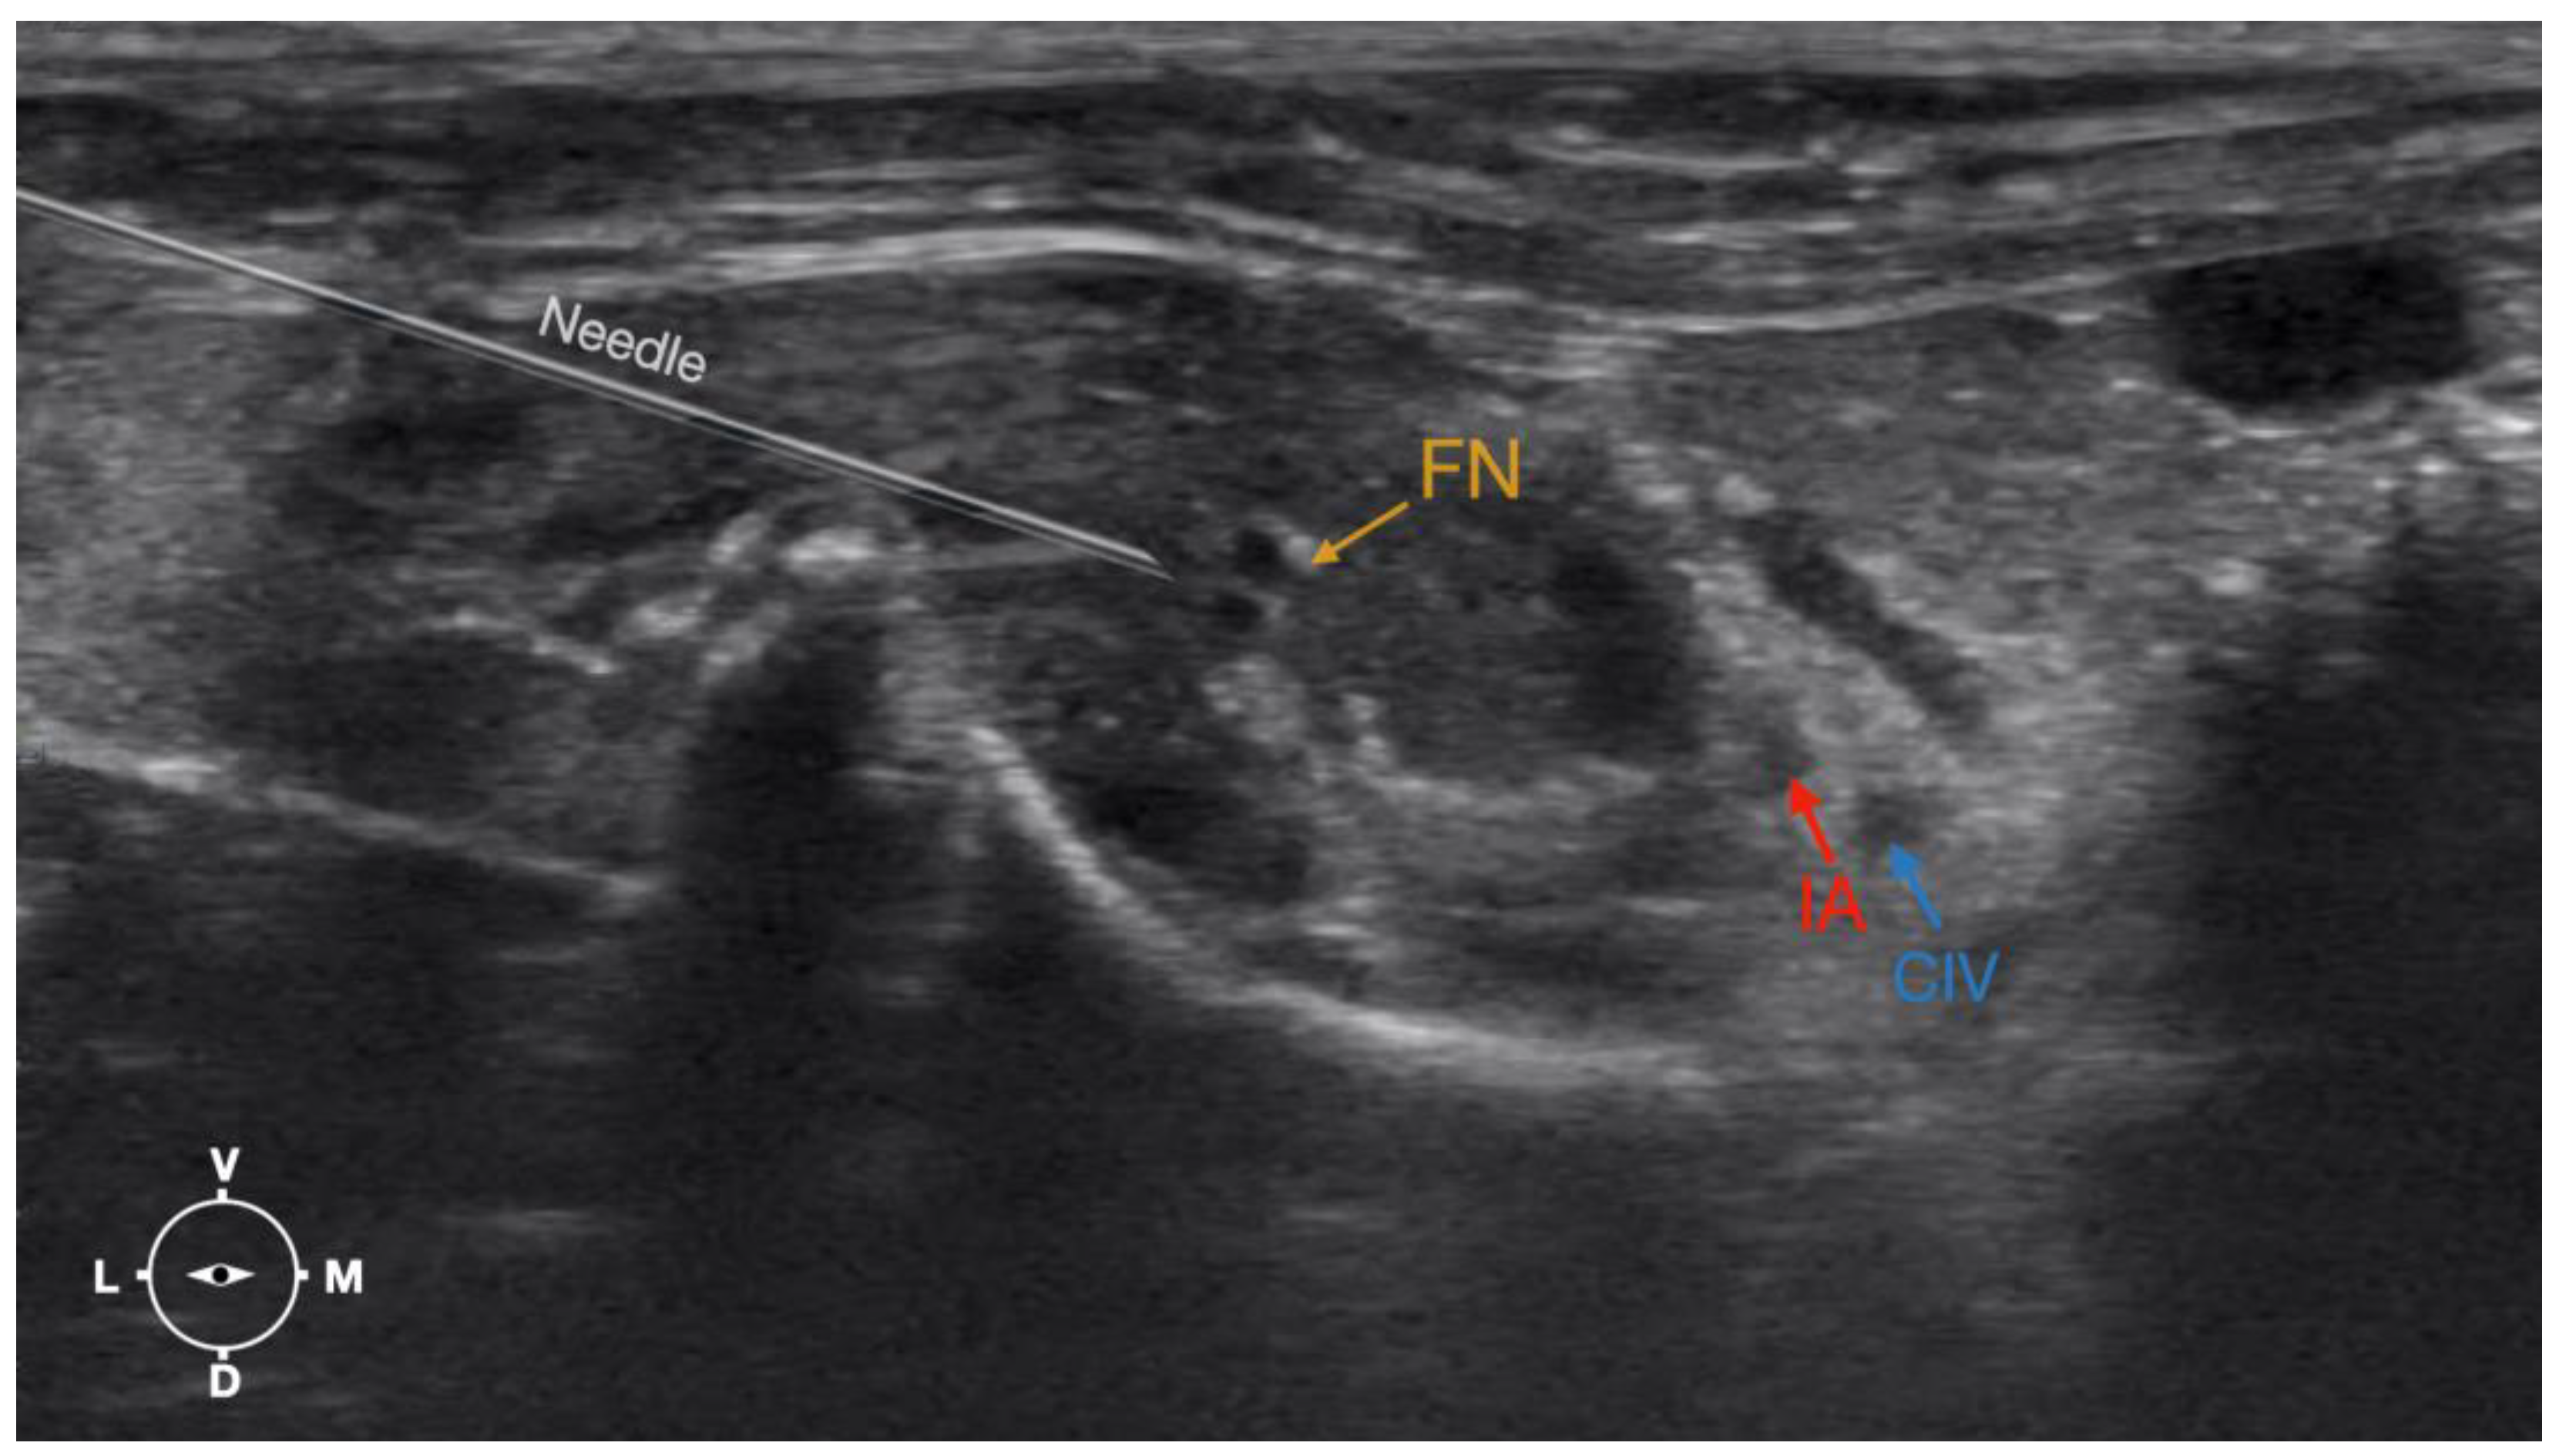

Figure 6.

Ultrasonographic image demonstrating the approach of the needle towards the femoral nerve. The window of interest was set at a depth of 2 cm and the focus was at the level of the femoral nerve to optimize the image quality. IA, iliac artery, CIV, common iliac vein; FN, femoral nerve; D, dorsal; L, lateral; M, medial; V, ventral.

The cadaver was positioned in dorsal recumbency before the leg was extended caudally. The transducer was placed over the hypaxial muscles, transverse to the long axis of the spine, and at the level of the projection of the iliac crest. The window of interest was set at a depth of 2 cm to optimize the image. Then, the transducer was moved in caudal direction along the IPM until the femoral nerve was clearly seen in the substance of the IPM (Figure 4). A 50 mm 22-gauge insulated needle (Sonoplex Stim Cannula, Pajunk Medical Produkte GmbH, Germany) prefilled with a L-NMB solution was inserted using an in-plane approach. The needle was inserted at the lateral edge of the transducer and advanced in-plane under sonographic guidance through the iliac fascia and IPM in a dorso-medial direction towards the femoral nerve (Figure 5 and Figure 6). The needle was advanced until its tip was located in vicinity of the femoral nerve. A test volume of 0.05 mL of L-NMB was injected to confirm adequate distribution. The remaining volume of 0.15 mL/kg was then injected extraepineurally around the femoral nerve.

Based on the anatomical dissection and the US scans performed in this phase, the best way to locate and inject the FN was achieved by scanning the IPM from the projection of the iliac crest in the caudal direction. Ultrasonographically, the femoral nerve appeared as a hypoechoic structure in the dorsal part of the IPM, becoming hyperechoic/honey-comb-like in the ventral part of the mentioned muscle. The IPM was displayed as structures with heterogeneous echogenicity. The ilium and the vertebrae were displayed as a hyperechoic structure with acoustic shadow and located lateral and dorsal to the femoral nerve, respectively.